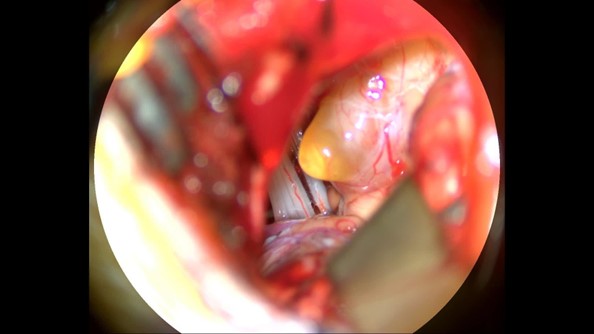

Although the three treatment options each had pros, cons and risks, Mr. Leung chose minimally invasive surgery in the end. Under four hours of general anesthesia, the neurosurgeons monitored Mr. Leung’s auditory nerve conduction function uninterruptedly during the operation.

Under the microscope, the neurosurgeons carefully remove and separate the five millimeters tumor from the auditory nerve using a one- to two-millimeter microscopic surgical instrument. After the operation, Mr. Leung’s hearing and facial nerve functions were able to remain intact, and no more suffering from tinnitus day and night.